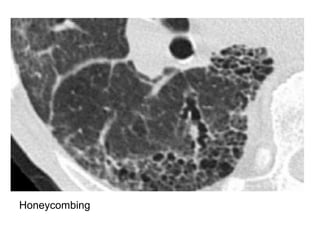

Honey combing

-Defined by the presence of small cystic spaces

with irregularly thickened walls composed of

fibrous tissue

-Honeycomb cysts often predominate in the

peripheral and subpleural lung regions

regardless of their cause

-Subpleural honeycomb cysts typically occur in

several contiguous layers, this finding can allow

honeycombing to be distinguished from

paraseptal emphysema in which subpleural

cysts usually occur in a single layer

Honeycombing & traction bronchiectasis in UIP

Honeycombing comprises reticular densities caused by the thick walls of the cysts.